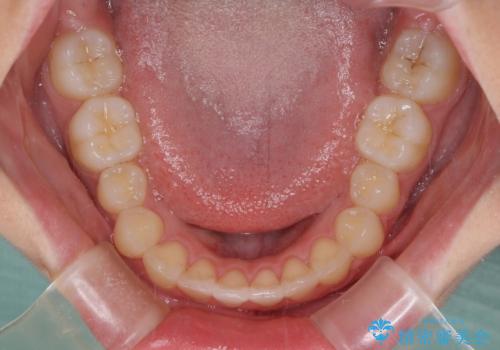

- 口元のデコボコを気にして来院された患者様です。

前歯の捻れにより口元が閉じにくくなっていたため、歯列全体の側方への拡大と、歯と歯の間を少し削ってスペースを獲得することとしました。

ゴムかけをしっかりと行ってもらい、スッキリとした口元に仕上げることができました。